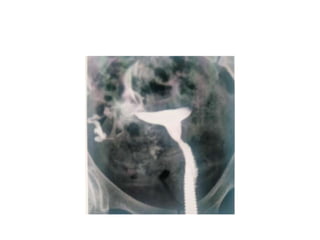

FISTULOGRAM

• A sinogram or fistulogram is a special x-ray

procedure , to visualize abnormal passage-

fistula/sinus in body

• following the injection of contrast media

• TECHNIQUE

• A preliminary film taken- to exclude foreign

body

• The pt lines supine with opening of

sinus/fistula uppermost

• The surrounding skin should be aseptic

-If discharge of pus/mucous- then only contrast

injected

-If drainage tube is insitu-introduced through it

or cannula of appropriate size is inserted through

orifice

-gauze pad around site of entry to prevent reflex

-sufficient quantity of water soluble contrast- to

outline the extent of lesion

Tracheo-oesophageal fistula

Rectovaginal fistula